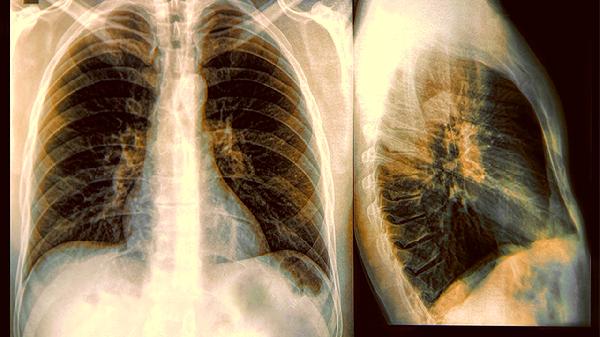

肺结节就是肺部出现的圆形或椭圆形小病灶,通常不超过三厘米。它们如同春天刚落下的嫩芽,有的只是肺部留下的"纪念品",有的是免疫系统的战果展示。大部分情况下不需要特别处理,只要定期复查就好。

根据成分不同分实性结节、磨玻璃结节和混合性结节三种类型。磨玻璃结节听起来文艺,其实就像隔着毛玻璃看东西,边缘模糊但整体透亮。不同类型的结节风险程度不同,需要专业判断。